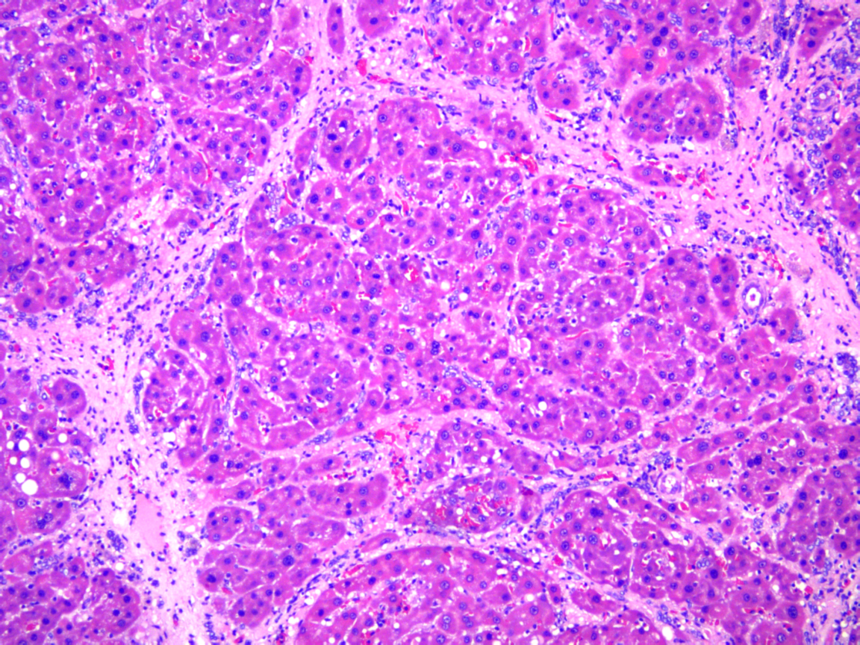

模型成功后,肝脏的病理变化显著:肝细胞破坏明显,相邻的肝脏组织中可见慢性炎细胞浸润;局部或者大部分产生被纤维隔包裹的结节性病变,胆管增生,胆管纤维化。

正常 肝硬化1 肝硬化2